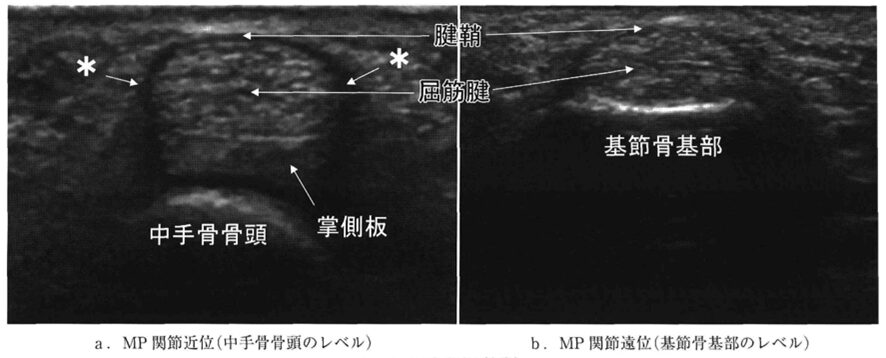

ばね指の診断においてエコーを用いると、炎症を起こして分厚くなった腱や腱鞘の状態、腱の滑走が悪い様子、周辺の血流が増加している様子などを、患者さんご自身の目で直接確認することができます。これにより、診断の正確性が格段に向上するだけでなく、ご自身の身体の中で何が起きているのかを深く理解し、納得して治療に進んでいただくことができます。

a:ばね指のエコー所見:腱鞘(黒い部分)が肥厚している

b:健常者のエコー所見:腱鞘(黒い部分)が薄い

出典:亀山真. 2012. 狭窄性屈筋腱腱鞘炎の超音波診断. MB Orthop. 25(8): 53-59.